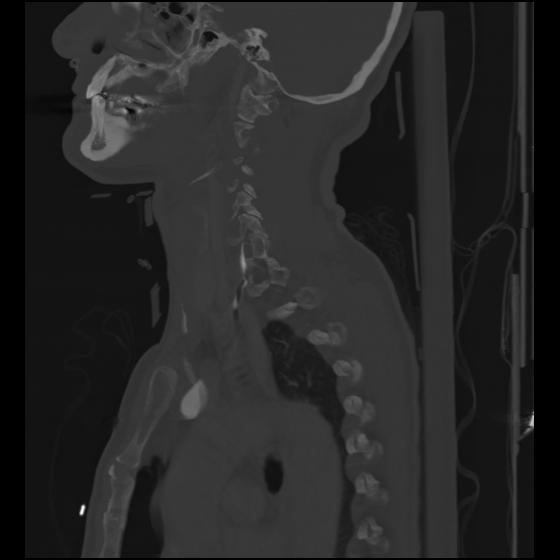

24 ANGIO,CE,Sag-MIP,5.000,ANGIO,Sag-MIP,